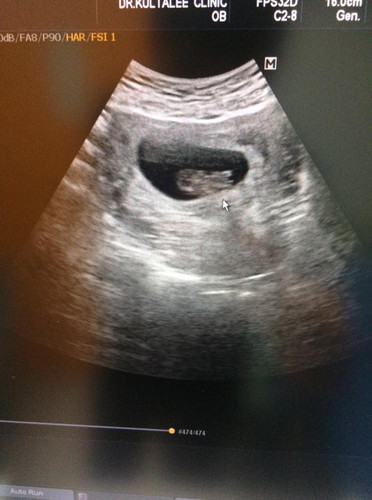

10w 6 d ????